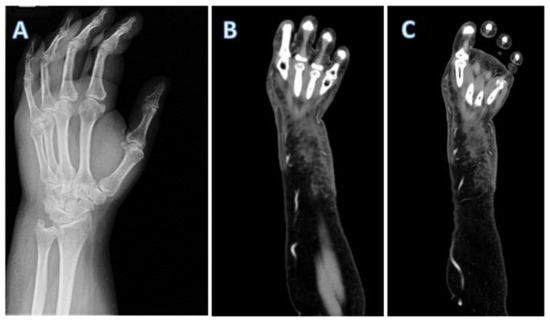

Introduction: Acute suppurative thyroiditis (AST) is an uncommon but potentially life-threatening condition. The majority of AST cases are caused by bacterial infection. Streptococcus suis is a swine pathogen that mostly causes meningitis and septice...